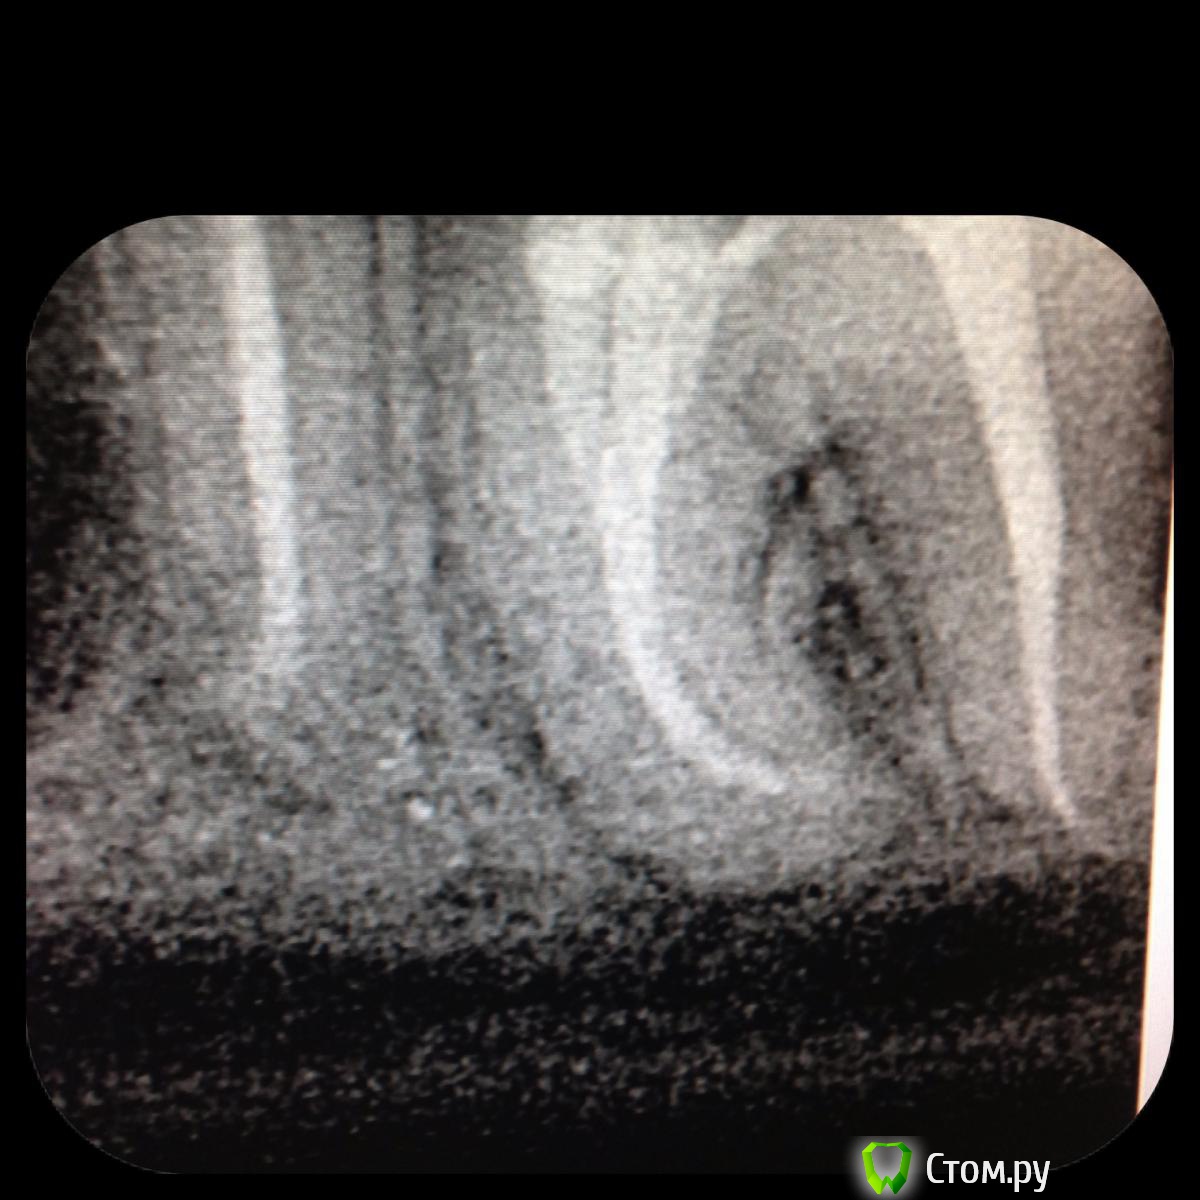

SSTi Опубликовано 27 июня, 2014 Автор Поделиться Опубликовано 27 июня, 2014 Латералю. 0.2 гуттой. Здесь мш 40.02 и еще штук 6-7 25.02 и 20.02. Ссылка на комментарий